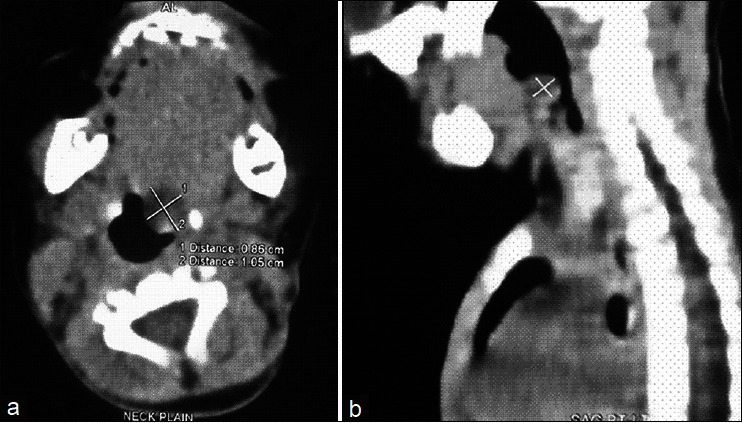

Vallecular cyst is a rare cause of upper airway obstruction in infants and children and presentation like acute stridor with near fatal respiratory distress is extremely rare. It is one of the rare causes of difficult intubation, during which cyst aspiration can improve the access. Vallecular cyst is commonly managed using microlaryngoscope and specialized instruments. We hereby report a method of endoscopic management of these cysts using conventional laparoscopic instruments.

Abstract Image